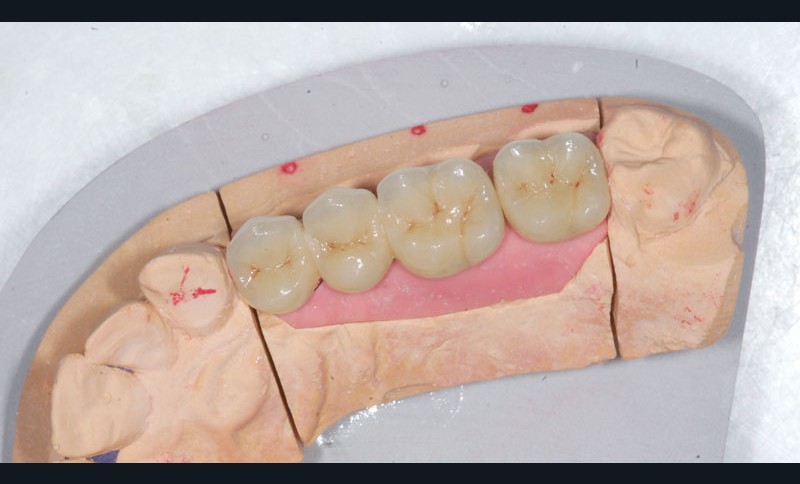

Le modèle de travail est fabriqué au laboratoire, des piliers CFAO Atlantis™ sont réalisés en fonction du bridge antagoniste transitoire.

Le bridge 24-26 céramométallique et la couronne unitaire sur 27 sont réalisés. Les piliers CFAO sont transvissés sur les implants, puis les éléments céramo-métalliques sont posés. Le résultat montre un parfait respect du projet prothétique en fonction de la courbe occlusale obtenue avec le bridge transitoire réalisé avec le ProtempTM 4 et une adaptation parfaite.